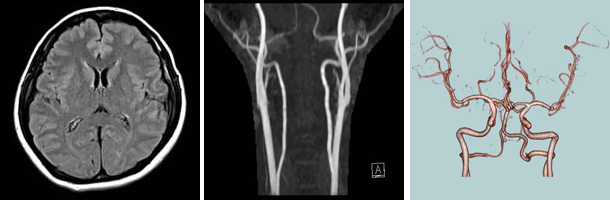

脳ドックではMRI、MRAによる画像診断を行い、脳疾患の早期発見・予防を目的としています。また、基本的な身体測定、血圧測定、血液検査、胸部レントゲン撮影、眼底写真撮影、精神知能検査も行い多方面から脳卒中の原因となる脳動脈硬化症などの危険性を探ります。

MRI(核磁気共鳴画像法)は電磁波を当てることで脳の内部を3次元画像としてモニターに写し、異常を調べることができる技術で、脳内の鮮明な画像を様々な角度から見る事が可能です。断層像も簡単に得ることができるため、病変部の位置や伸展範囲を目で見て判定できます。MRIによってわかる病気は、脳腫瘍、脳梗塞、脳萎縮、その他の頭蓋内病変などです。自覚症状の出にくい脳疾患を早期発見することができます。

MRA検査

MRA(磁気共鳴血管画像)はMRIを用いて、脳内の血管の様子だけを写し出し、詳しく観察できる技術です。3次元的に様々な角度から血管の様子を観察することができます。

このMRA検査によって、くも膜下出血の原因となる動脈瘤や脳動静脈奇形、脳梗塞の原因となる脳動脈硬化症、血管狭窄症などを見つけることができます。

また、頸部MRA検査も行います。首の左右の側部にある心臓から脳へと通じる大きな血管を頸動脈といいます。この部分で動脈硬化が起きて血管が詰まると、やがて血の塊や動脈硬化のかけらが脳の血管にまで流れて血管を塞ぎ、脳梗塞を起こす恐れがあります。頸動脈に動脈硬化や頸動脈狭窄などが起きていないかを調べることで、脳梗塞の兆候が分かります。